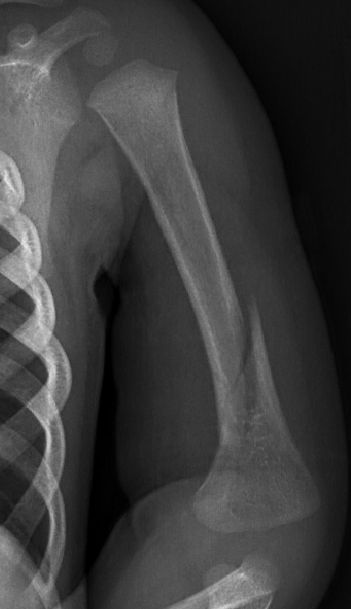

Skada barn: Fraktur humerusdiafys (barn)

1-årigt barn med diafysär humerusfraktur, fick vadd runt armen och linda runt kroppen i 3 veckor, därefter kliniskt läkt.